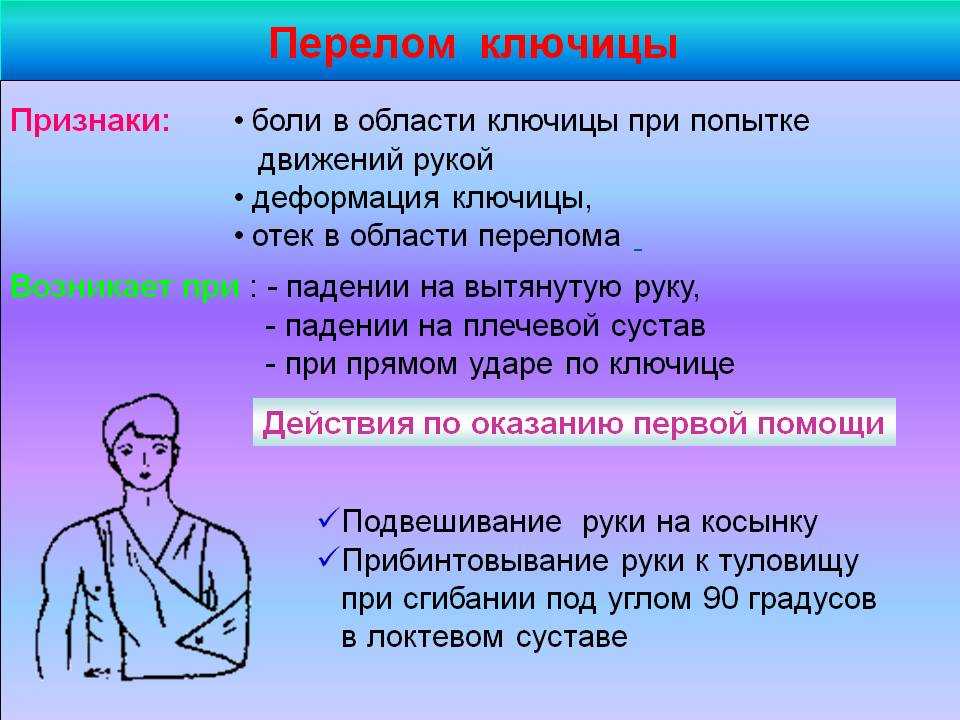

Вывихи и переломы ключицы презентация - 85 фото